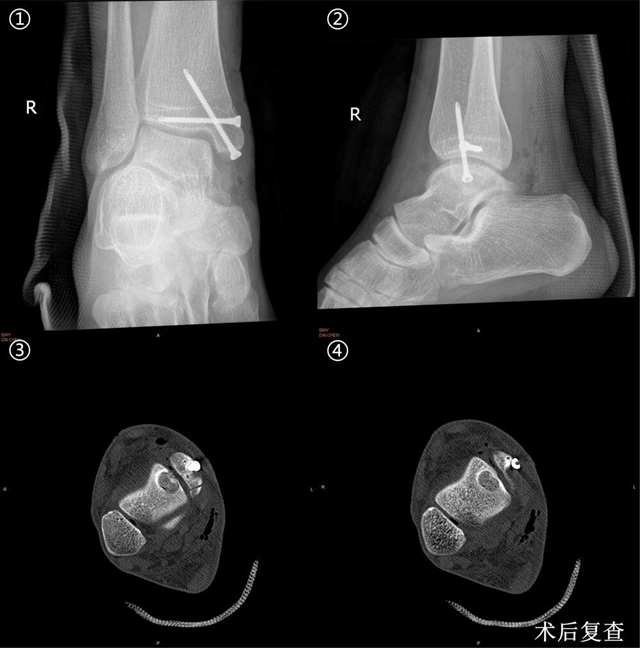

在科室副主任关钛元教授组织专家经过认真讨论后,认为其软骨损伤面积超过120m㎡,损伤深度超过12mm,并且伴软骨下骨囊肿形成,分型为Hepple V型,保守治疗及微骨折术治疗疗效有限,后期可能发展为创伤性踝关节炎,张磊教授建议行“踝关节镜检清理+新型半斜型内踝截骨+取同侧膝关节软骨行马赛克软骨移植术。”

相比传统截骨方式,更有利于复位及截骨断端固定,两枚垂直交叉螺钉进行固定,抗旋转力和剪切力更强,显著提升固定效果。